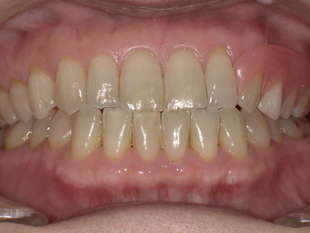

■ 【Before→After】ノンクラスプ義歯で口元の印象が大きく若返り

▼ 治療前

-

歯の欠損部の影響で口元がへこみ、老けた印象

バネ式の入れ歯では金具が見えてしまう

噛み合わせが不安定で、しっかり食べられない

▼ 治療後(ノンクラスプデンチャー装着)

歯ぐきの色に馴染む樹脂で金具ゼロの自然な見た目

厚みが薄く、軽いため痛みほぼゼロの快適さ

義歯のフィット感が高く、噛む力も安定

口元がふっくらし、見た目・印象が10歳以上若返る